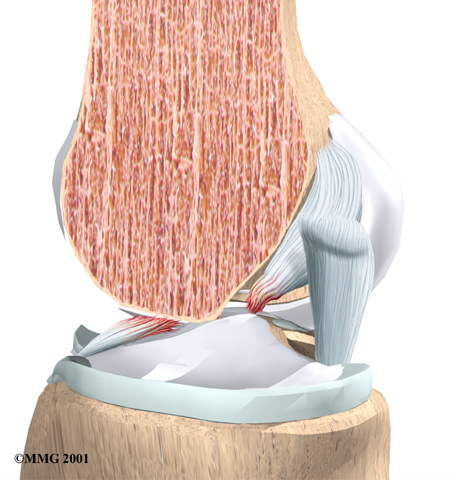

The ACL is the main controller of how far forward the tibia moves under the femur. This is called anterior translation of the tibia. If the tibia moves too far, the ACL can rupture. The ACL is also the first ligament that becomes tight when the knee is straightened. If the knee is forced past this point, or hyperextended, the ACL can also be torn.

Other parts of the knee may be injured when the knee is twisted violently, as in a clipping injury in football. It is not uncommon to also see a tear of the medial collateral ligament (MCL) on the inside edge of the knee, and the lateral meniscus, which is the U-shaped cushion between the outer half of the tibia and femur bones.